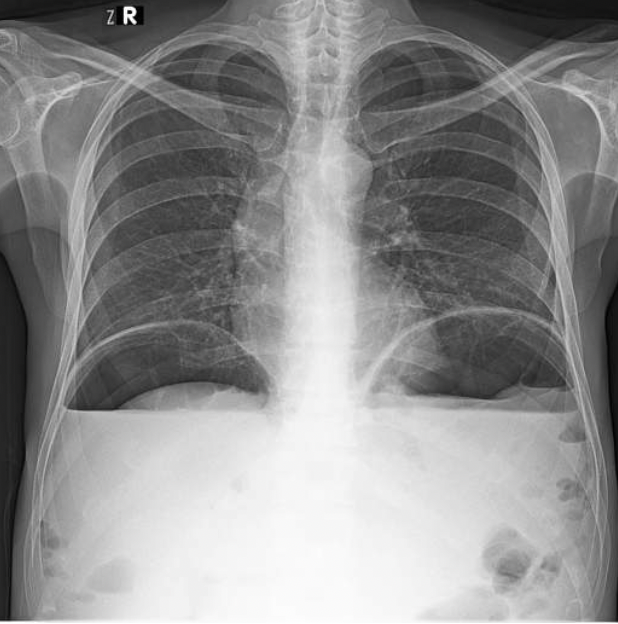

What do you think that free air under the diaphragm might indicate?

Free air under the diaphragm may suggest a possible perforation of the bowel (either stomach or gut as they hold air in these spaces) and this can lead to air leaking out and building up under the diaphragm.

There is also possible duodenal ulcers or peptic-duodenal ulcers which may also possibly be the cause of this.

Free air is example of pneuomoperitoneum.

The diagram of the X-ray shows how air build up under the diaphragm causes air to push up against arched diaphragm and flattens the muscle.

Why do we do an erect chest x-rays in humans?

This allows air to rise to top of the abdomen and the air is seen delineating the diaphragm (i.e. you can see both sides of the diaphragm where usually only one would be visible.

If the individual is too unwell to stand for a chest x-ray, a lateral decubitus film will do the same as the lateral abdominal radiograph in dogs.